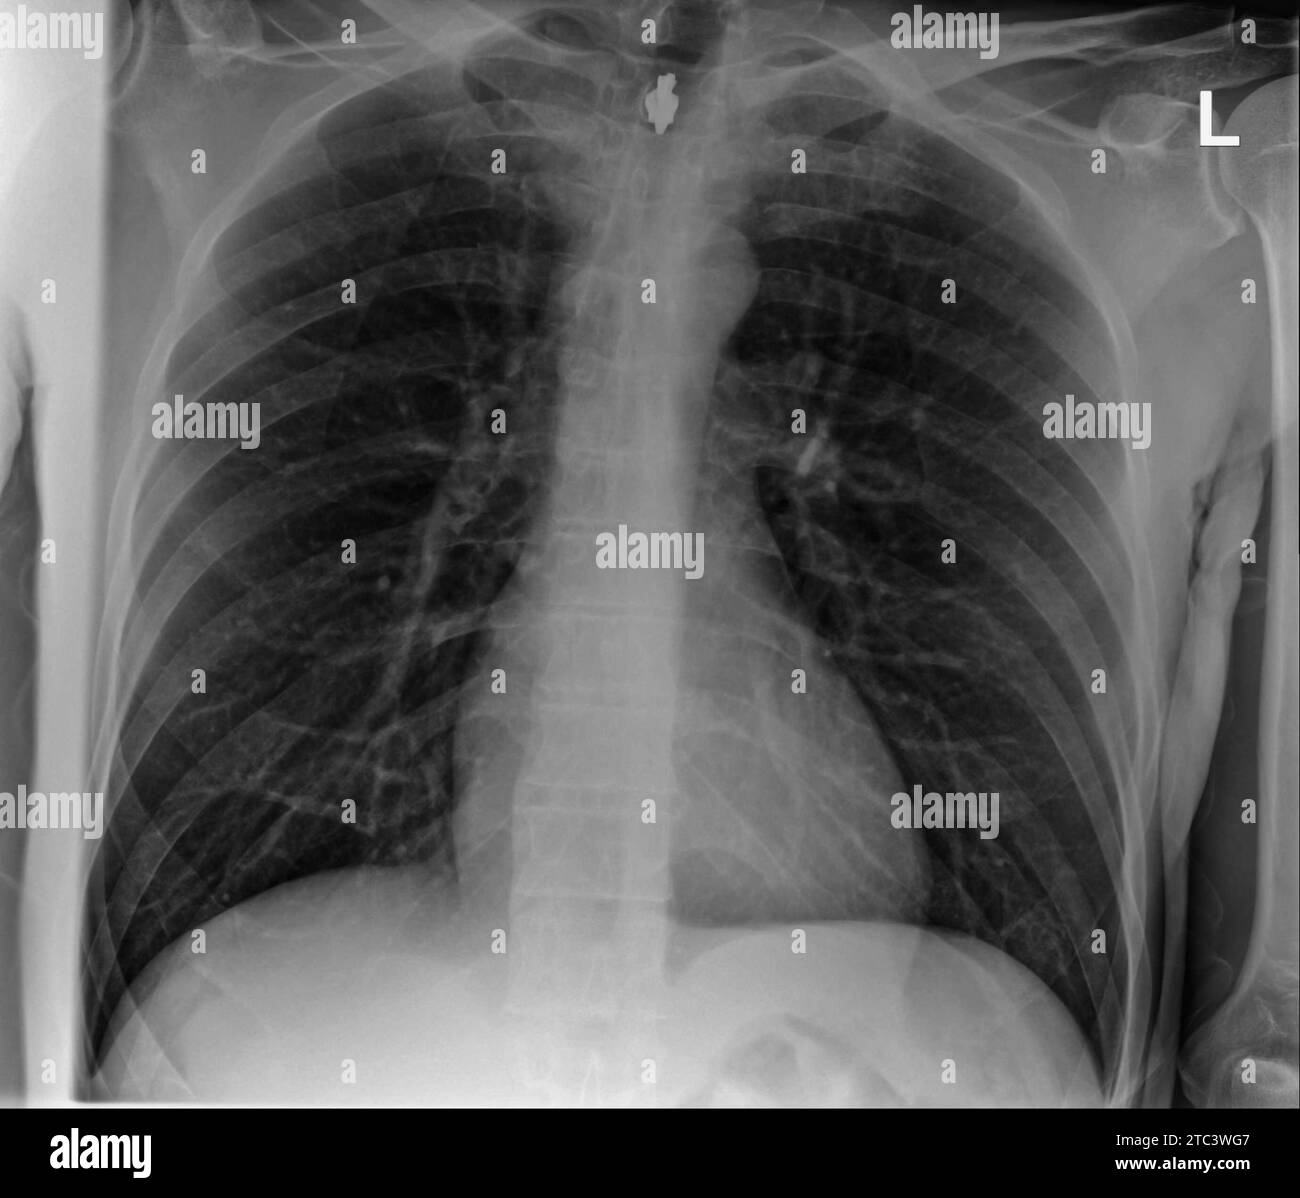

Film chest xray show interstitial infiltration both lung Stock Photo Does Thoracic X Ray Show Lungs Expect to see a lot of black—that's the air in your lungs, interlaced with delicate white lines that map out your airways and blood vessels. Life threatening diagnosis like aortic dissection (tear of aorta into two), pulmonary embolism (clot to the lung) and heart. Chest pain may be a symptom of a serious condition. The readings are compared with normal. Does Thoracic X Ray Show Lungs.

Film chest xray show interstitial infiltration both lung Stock Photo Does Thoracic X Ray Show Lungs Life threatening diagnosis like aortic dissection (tear of aorta into two), pulmonary embolism (clot to the lung) and heart. Chest pain may be a symptom of a serious condition. Expect to see a lot of black—that's the air in your lungs, interlaced with delicate white lines that map out your airways and blood vessels. The readings are compared with normal. Does Thoracic X Ray Show Lungs.